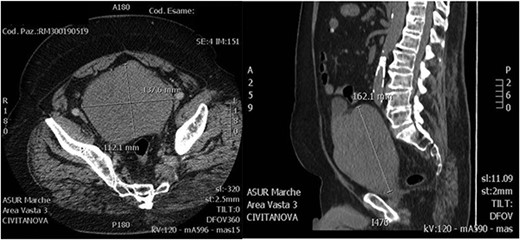

A 72-year-old man was admitted to the emergency department complaining bilateral flank pain and severe lower urinary tract symptoms (LUTS). His International Prostatic Symptoms Score (IPSS) was 27. His past medical history showed alcohol abuse, stage II chronic kidney disease, atrial fibrillation complicated by pulmonary embolism and stroke. His body mass index was 35. He was on Rivaroxaban therapy. Rectal examination showed a significantly enlarged prostate, with a smooth surface and with no nodularity. He underwent an abdominal ultrasound that showed bilateral grade III hydroureteronephrosis and a huge prostate, with negligible post-void residual urine. Laboratory tests showed a serum creatinine of 2.61 mg/dl, PSA 6.19 ng/ml and no electrolytes imbalance. Uroflowmetry was performed showing a Q max 9 ml/s, Volume void 180 ml and RPM 15 ml. He started therapy with Dutasteride 0,5 mg and Silodosin 8 mg. An abdominal contrast-enhanced computed tomography (CT) scan was performed to evaluate bilateral hydronephrosis, and showed persistent dilatation of the collecting system and ureters bilaterally, with thinning of the bilateral cortical and an estimated prostate volume of 1280 ml (Fig. 1). A percutaneous nephrostomy was placed bilaterally and anterograde pyelography was performed, showing extreme tortuosity of the ureters. Serum creatinine decreased to 1.25 mg/dl 1-month later, and the nephrostomies were closed. A multiparametric magnetic resonance imaging (MRI) of the prostate was performed showing that the peripheral zone was not recognizable and the transition zone was occupied by a huge adenoma. After 3 months of combination therapy, the patient reported improvement in LUTS (IPSS 15, QoL2). Then, he underwent anterograde pyelography that showed poor contrast medium progression. Subsequently, percutaneous nephrostomies were replaced with double J stents. Two months later, a decrease of bilateral hydronephrosis was demonstrated and serum creatinine remained stable at 1.20 mg/dl. After 6 months, patient’s creatinine was 1.22 mg/dl and he was scheduled for retrograde stent replacement with flexible cystoscope. Uroflowmetry was repeated showing a Q max 23.8 ml/s, Volume void 213 ml and RPM 40 ml.